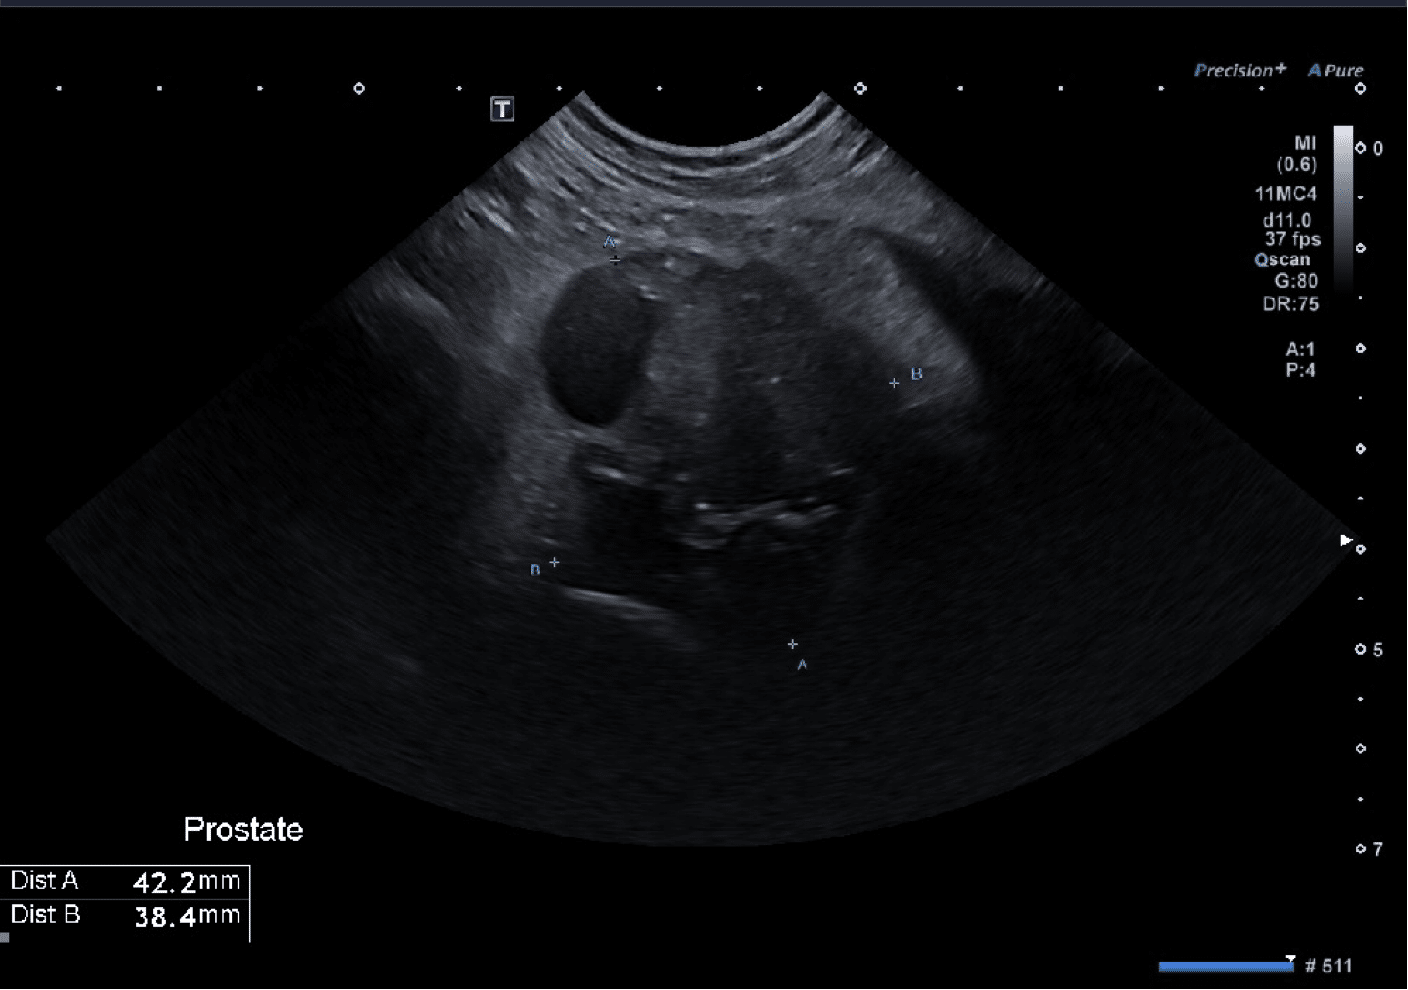

Compte-tenu de ces éléments, une exploration échographique de l’appareil uro-génital est entreprise. L’échographie révèle une prostate de taille augmentée (38 x 42 mm), de contours irréguliers, avec un effacement du sillon médian. Le parenchyme est hétérogène avec des minéralisations et des plages hypoéchogènes (Figure 1).

Figure 1 : Prostate visualisée à l’échographie abdominale

L’association d’une prostatomégalie irrégulière, d’un parenchyme hétérogène avec minéralisations et de modifications vésicales oriente prioritairement vers un processus néoplasique prostatique avec possible extension vésicale secondaire.

Le diagnostic différentiel principal est un carcinome prostatique (carcinome ou adénocarcinome), issu du parenchyme ou de l’urètre prostatique, avec infiltration secondaire de la vessie. Les critères échographiques observés — hétérogénéité marquée, minéralisations intraparenchymateuses, perte de l’architecture — sont fortement compatibles avec cette hypothèse [2].